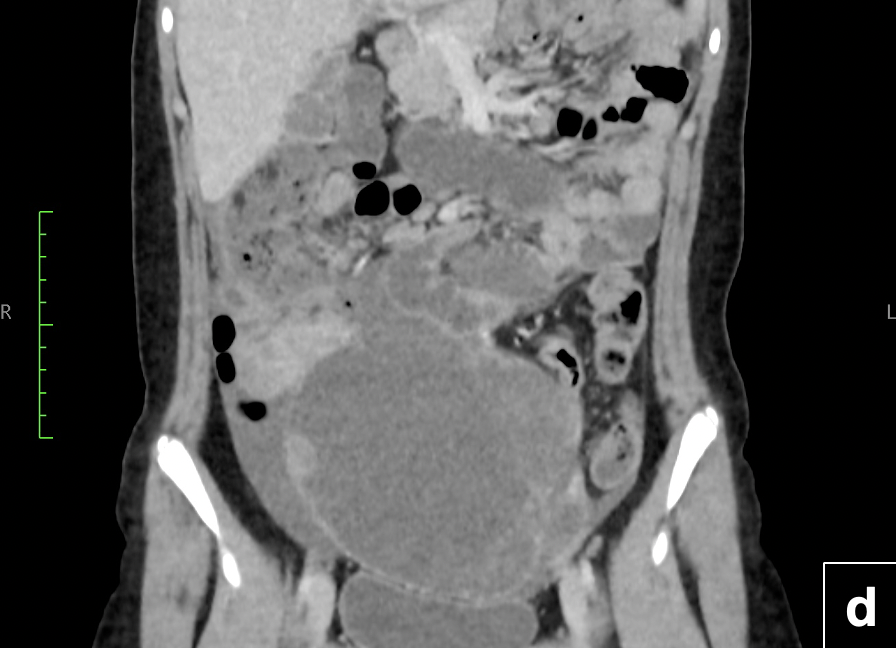

TC de abdomen y pelvis: (d) y (e): estudio coronal y axial con contraste que evidencia tumor sólido de íleon distal, con extenso componente sólido – quístico que se aloja en el hemiabdomen inferior. Se observa realce heterogéneo del componente solido (flecha). También es posible visualizar leve cantidad de líquido peritoneal y mayor densidad del tejido adiposo circundante.